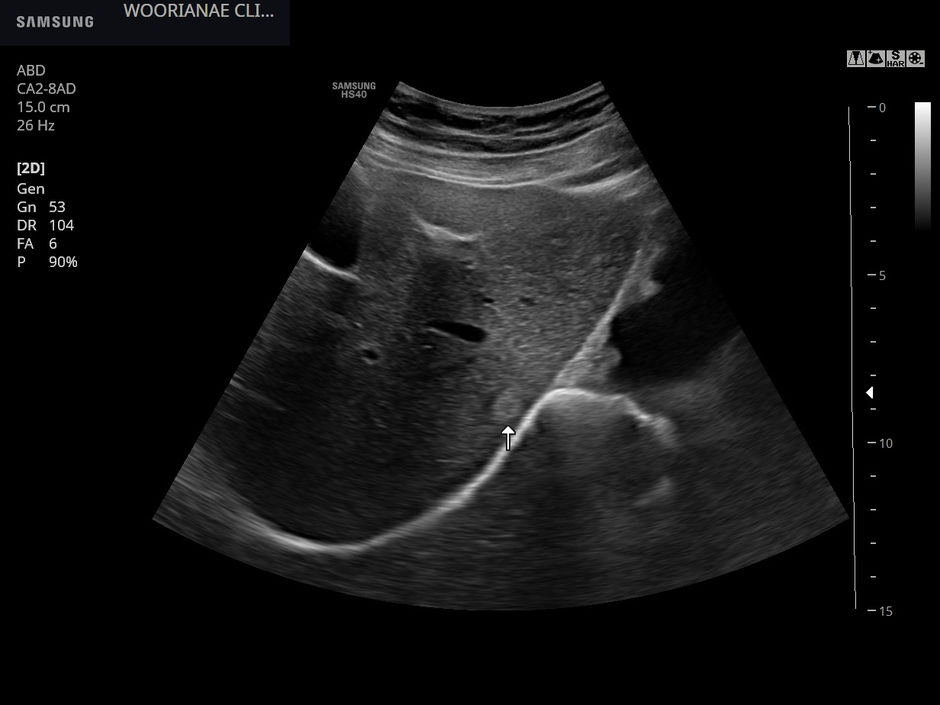

비특이적인 왼쪽 등 통증, spasm? 연축? 걱정에 대한 초음파 평가 - 동대문구 답십리, 장안동, 우리안애 우리안愛 내과

50대 후반 여자, 장안동 4거리에서 찾아서, 검색해서 방문 간질환으로 A 대학병원, 관절 질환으로 B 대학병원 추적중 약 2주전부터 왼쪽 등쪽 (흉곽의 아래쪽, 광배근, latissimus dorsi 에 해당하는?) 이 쪼이면서 아프더라....